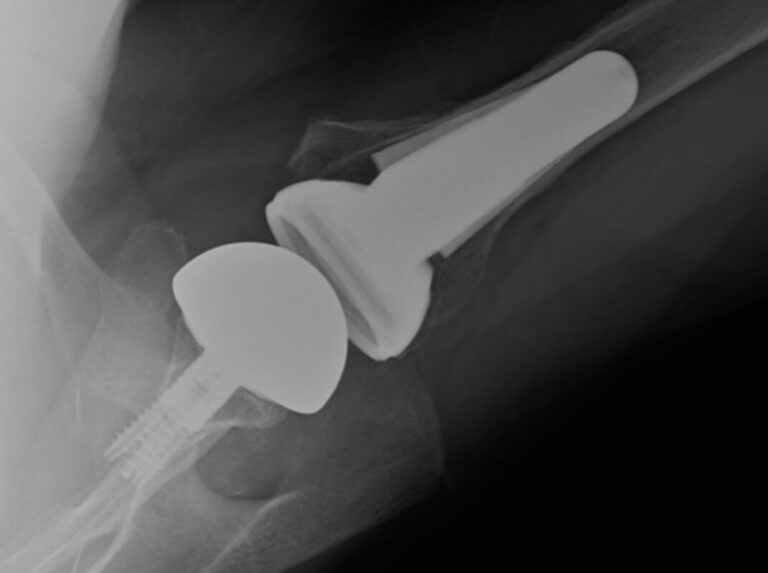

DePuy, Delta